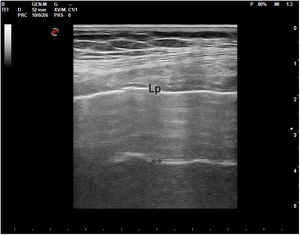

En la ecocardiografía se utilizan sondas sectoriales de baja frecuencia (2 a 5MHz), parecidas a las convex pero con una superficie de contacto con la piel mucho más pequeña, lo que permite evitar la sombra acústica que producen las costillas y mejorar la visión (fig. 1).

En el pulmón, la ecografía se comporta como un densitómetro. En un pulmón aireado (ya sea normal o con hiperaireación, como ocurre en el enfisema), la gran diferencia de impedancia acústica entre la pared torácica y el aire no permite obtener una imagen anatómica. En este caso, se evidencia la línea pleural, una franja horizontal hiperecogénica altamente reflectante del haz de ultrasonido. En el corte longitudinal (fig. 13), la línea pleural aparece entre 2 costillas sucesivas, en el denominado signo del murciélago: las corticales de las costillas, hiperecogénicas y con sombra posterior, constituirían las alas del murciélago, y la línea pleural, el cuerpo. En el corte oblicuo o intercostal (fig. 14), la línea pleural se presenta en su máxima extensión. Es una estructura dinámica, que se desliza con los movimientos respiratorios en el denominado deslizamiento (o «sliding») pleural. Al tratarse de una superficie altamente reflectante del ultrasonido, genera unos artefactos en profundidad, denominados líneas A. Las líneas A son hiperecogénicas, horizontales y paralelas, siempre a la misma distancia entre ellas (que es la misma distancia que hay entre la línea pleural y la sonda). Su presencia indica que la sonda está colocada perpendicular a la pleura, y no traduce enfermedad.